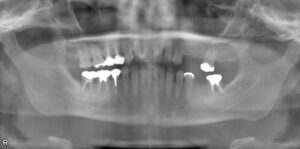

上下顎臼歯3本欠損症例

BEFORE AFTER 50歳男性/上2本・下1本欠損/インプラント埋込手術 【治療内容】 左上第一・二小臼歯の欠損部…